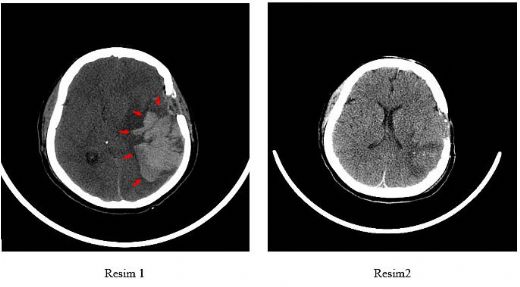

Beyin Zarı Kanaması: Belirtileri ve Tedavisi Beyin zarı kanaması, beyin zarı olarak adlandırılan üç tabakalı zarın (dura mater, arachnoid mater ve pia mater) arasında meydana gelen kanama durumudur. Bu durum, genellikle travma, yüksek tansiyon, anevrizma veya damar malformasyonları gibi çeşitli nedenlerden kaynaklanabilir. Beyin zarı kanaması, acil tıbbi müdahale gerektiren bir durumdur ve çoğu zaman ciddi sağlık sorunlarına yol açabilir. Belirtileri Beyin zarı kanamasının belirtileri, kanamanın yerleşimi ve ciddiyetine bağlı olarak değişiklik gösterebilir. Genel olarak, aşağıdaki belirtiler gözlemlenebilir:

Bu belirtiler, acil bir durumun habercisi olabilir ve derhal tıbbi yardım alınması gerekmektedir. Tanı Yöntemleri Beyin zarı kanamasının tanısı genellikle aşağıdaki yöntemlerle konulur:

Tedavi Yöntemleri Beyin zarı kanamasının tedavisi, kanamanın nedenine, yerleşimine ve ciddiyetine bağlı olarak değişiklik göstermektedir. Tedavi yöntemleri arasında: